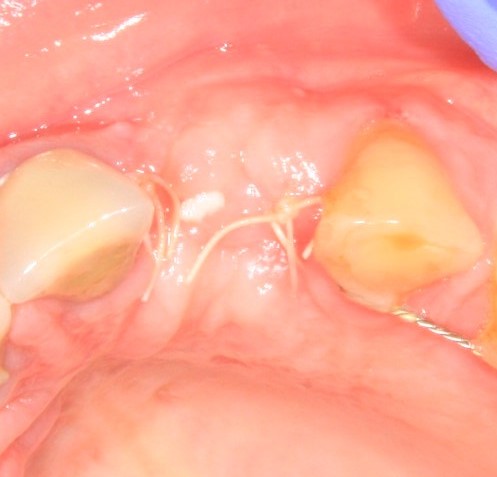

Давайте внимательно посмотрим на состояние лунок центральных резцов после удаления:

Приемлемый фенотип (сочетание толщины и ширины участка жевательной десны) — это, конечно, приятно. Но гораздо важнее сосредоточиться на рисках, их на этот момент два:

— травматическое повреждение слизистой, вызванное удаление зубов связано с тем, что при хроническом воспалении слизистая оболочка теряет эластичность, поэтому легко рвётся. Такая ситуация создаёт серьёзную угрозу эстетическому результату лечения, в зависимости от того, насколько быстро десна придёт в норму.

— как и предполагалось после КЛКТ, утрата костной стенки привела к тому, что десна провалилась в просвет лунки левого центрального резца. Это еще больше усугубляет клиническую ситуацию.

Для нас это не было неожиданностью. Зная закономерности изменений тканей при хроническом  воспалении и данные КЛКТ, мы можем довольно точно предсказывать развитие клинической ситуации и соответственно к ней подготовиться. Именно поэтому, помимо обычной немедленной имплантации, мы запланировали аугментацию лунки с помощью биоматериалов и метода трансплантации лоскута (см. предварительные планы лечения).